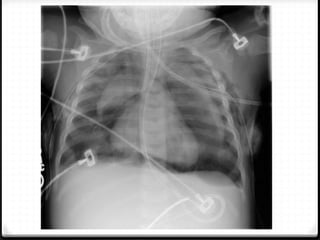

Pneumothoraks

0 Udara pada rongga pleura

0 15%–40% ditemukan pada trauma thoraks

0 Ruptur alveoli karena ada tekanan meninggi secara tiba-tiba

pada intrathorakal akibat trauma dengan atau tanpa fraktur

costae

0 Radigrafi polos >>

0 ± 10% tidak dapat dievaluasi dengan radiografi polos  CT scan

Tension pneumothoraks

Pneumothoraks 0 Udara padarongga pleura 0 15%–40% ditemukan pada trauma thoraks 0 Ruptur alveoli karena ada tekanan meninggi secara tiba-tiba pada intrathorakal akibat trauma dengan atau tanpa fraktur costae 0 Radigrafi polos >> 0 ± 10% tidak dapat dievaluasi dengan radiografi polos  CT scan